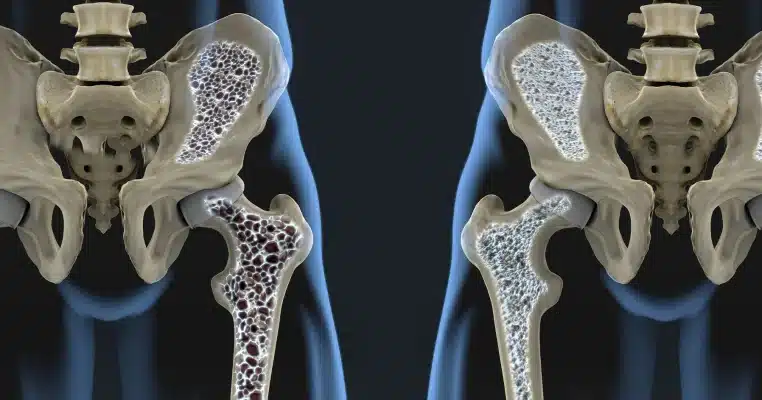

Δέκα εκατομμύρια Αμερικανοί έχουν οστεοπόρωση, μια ασθένεια που προκαλεί τα οστά να γίνονται εύθραυστα και αδύναμα. Περίπου το 20 τοις εκατό όλων των πασχόντων είναι άνδρες, σύμφωνα με το Εθνικό Ίδρυμα Οστεοπόρωσης. Μια έκθεση που δημοσιεύτηκε στο Archives of Internal Medicine διαπίστωσε ότι πολλοί Αμερικανοί άνδρες με οστεοπόρωση δεν λάμβαναν τη φροντίδα που χρειάζονταν.

Οι γιατροί στο Επισκοπικό Νοσοκομείο St. Luke’s στο Χιούστον παρακολούθησαν 363 ασθενείς που είχαν υποστεί μη τραυματικά κατάγματα ισχίου. Περίπου το ένα τρίτο ήταν άνδρες και η μέση ηλικία των ασθενών ήταν περίπου 80. Οι περισσότεροι άνδρες και γυναίκες έσπασαν τους γοφούς τους σε πτώσεις, υποδηλώνοντας ότι τα οστά τους ήταν αρκετά εύθραυστα. Δεδομένης της ηλικίας τους και της φύσης των τραυματισμών τους, οι περισσότεροι ειδικοί θα συμφωνούσαν ότι αυτοί οι ασθενείς θα έπρεπε να θεωρούνταν πρωταρχικοί υποψήφιοι για τη διάγνωση της οστεοπόρωσης. Ωστόσο, μόλις έλαβαν εξιτήριο από το νοσοκομείο, μόνο πέντε από τους 110 άνδρες ασθενείς — 4,5 τοις εκατό — έλαβαν θεραπεία για οστεοπόρωση, σε αντίθεση με το 27 τοις εκατό των γυναικών.

Οι ερευνητές του Χιούστον, με επικεφαλής τον φυσιολόγο των οστών Gary Kiebzak, έκαναν περιοδικούς ελέγχους στους ασθενείς για πέντε χρόνια. Το ποσοστό των ανδρών που υποβλήθηκαν σε κάποια μορφή αγωγής για την υγεία των οστών (συνήθως συμπληρώματα βιταμινών) τελικά αυξήθηκε στο 27 τοις εκατό. Αλλά το συγκρίσιμο ποσοστό για τις γυναίκες ήταν πολύ υψηλότερο — 71 τοις εκατό. Οι γυναίκες είχαν επίσης διπλάσιες πιθανότητες από τους άνδρες να λάβουν πιο επιθετικές θεραπείες, όπως συνταγογραφούμενα φάρμακα για την οστεοπόρωση και τεστ οστικής πυκνότητας. Στη μελέτη του Χιούστον, το 32 τοις εκατό των ανδρών ασθενών πέθαναν μετά από ένα χρόνο εξιτήριο, σε σύγκριση με το 17 τοις εκατό των γυναικών.